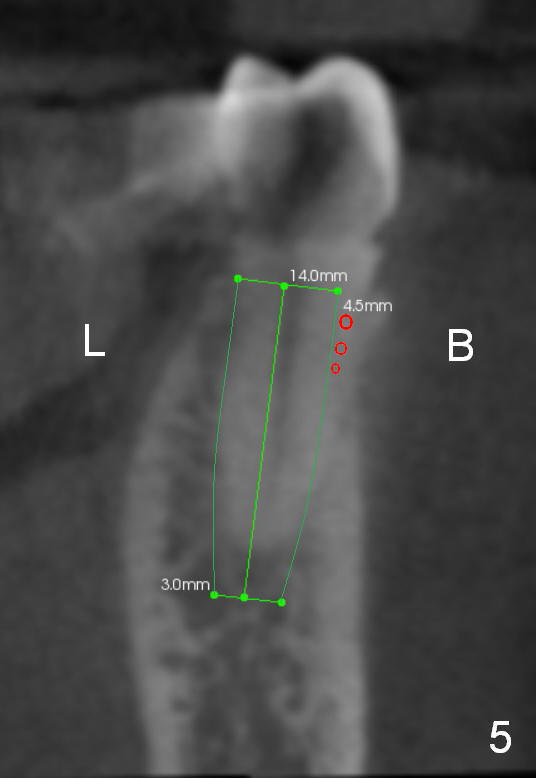

CT sagittal section of a similar case shows that the root is also long, but curved (Fig.4).  A 4.5x14 mm implant is slightly longer than the root.  The apex of the implant has distance to the underlying nerve (N).  The coronal section shows that the implant should be placed lingually (Fig.5 L), since the buccal (B) plate is thin (Fig.6 between arrowheads).  The first drill (2 mm) is to be placed lingually (Fig.7 red arrow).  When the implant is placed, there should be a buccal gap, to be filled with bone graft (Fig.5 red circles).

The 2nd drill will be 2.5 mm reamer (17 mm from the gingival margin).  To placed the implant, use a latch driver, followed by latch adapt and torque wrench.  If insertion torque is high (>45 Ncm), place cemented abutment (probably 5824 (Fig.3 green line (5.44 mm)) and fabricate an immediate provisional.